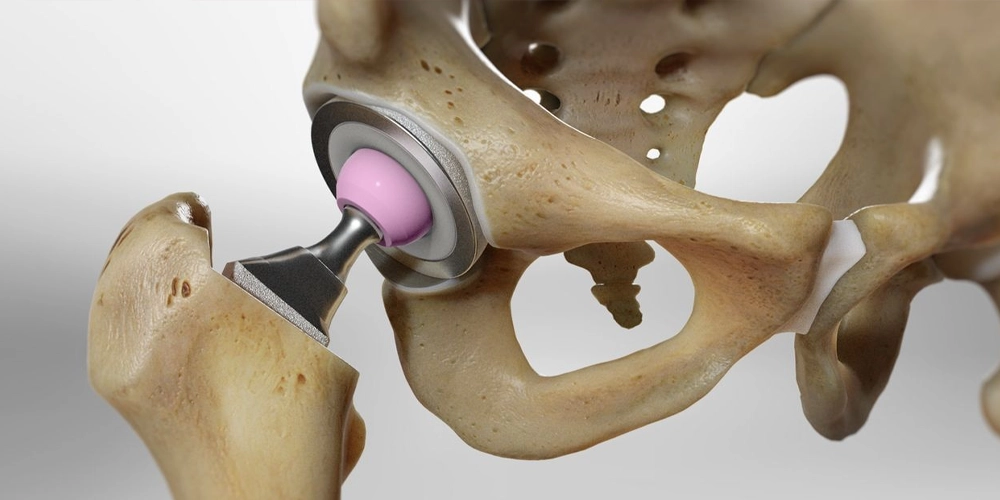

La chirurgie de remplacement de la hanche est une procédure orthopédique très efficace qui remplace une articulation de la hanche gravement endommagée par une articulation artificielle faite de matériaux durables comme le métal, la céramique ou le plastique. Cette chirurgie est une solution qui change la vie pour des conditions telles que l’arthrose avancée ou une fracture de la hanche, qui causent une douleur débilitante et une mobilité limitée. L’objectif principal de la chirurgie de remplacement de la hanche est d’éliminer la douleur, de restaurer la fonction articulaire et d’améliorer significativement la qualité de vie d’une personne.

- Procédure : Chirurgie de remplacement de la hanche (Prothèse de la hanche).